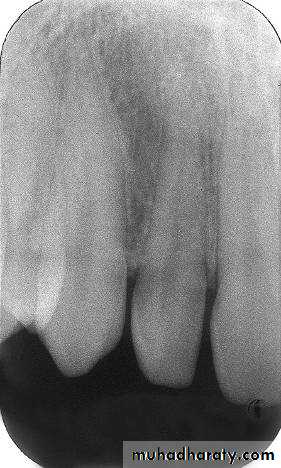

The molar-bitewing. A, Film placement. B, Resultant radiograph.

A

B